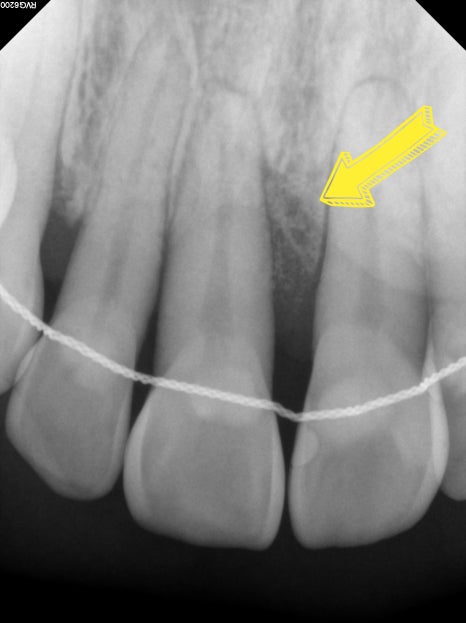

CASE 2. "앞니 잇몸이 내려가서 보기 싫어요"

앞니 부위의 잇몸뼈 소실이

비교적 크게 진행되어

치아 뿌리가 많이 노출된 상태로

기능적인 불편감 보다는

심미적인 부분에 고민이 되셔서 내원하셨습니다

다행히 치아의 흔들림은 크지 않은 상태였으며

담당 원장님 진단 하에

엠도게인 치주 재생 치료를 진행하였습니다

치료 후 약 1개월 경과 시

잇몸뼈 재생이 진행되는 양상을

관찰할 수 있었으며,

자연치아 보존 가능성을

함께 지켜볼 수 있었던 사례입니다